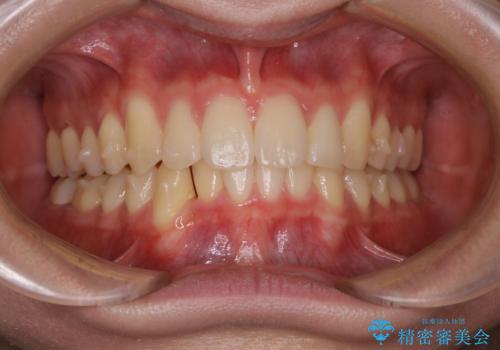

- 口元の突出感は気にならないが、上の前歯の角度と、下の前歯のがたつきが気になるとご相談にいらした方です。なるべく費用や治療期間を抑えて治療したいとのご希望に合わせて治療を計画しました。

この患者様への治療方針として、奥歯から少しずつ歯を移動させる方法と、歯をわずかに削って並べる方法とをご提案しました。短期間での治療を望まれたため、歯をサイズダウンさせて歯を並べました。わずかではあるものの、削った歯は元には戻せないことを十分ご説明し、ご理解ご了承を頂いた上で治療を行いました。